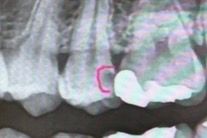

작은 어금니 레진으로 치료 불가능할까요

이 치아인데 저거 레진치료는 불가능할까요? 꼭 인레이로 해야할까요… 그리고 만약 신경치료 하게된다면 무조건 크라운 해야하는건가요??

충치가 상당히 깊어 보입니다. 충치제거시 신경이 노출되면 인레이로 치료를 어려울것같습니다.

사진으로 봤을 경우 인접면의 충치가 것으로 보입니다. 우선 충치를 제거했을때 신경이 노출이 된다면 신경치료의 가능성이 있으며 충치의 크기로 봤을경우 크라운 치료를 할 가능성이 높아보입니다.

-> 레진 시도는 해볼 수 있습니다

그리고 만약 신경치료 하게된다면 무조건 크라운 해야하는건가요?? -> 네